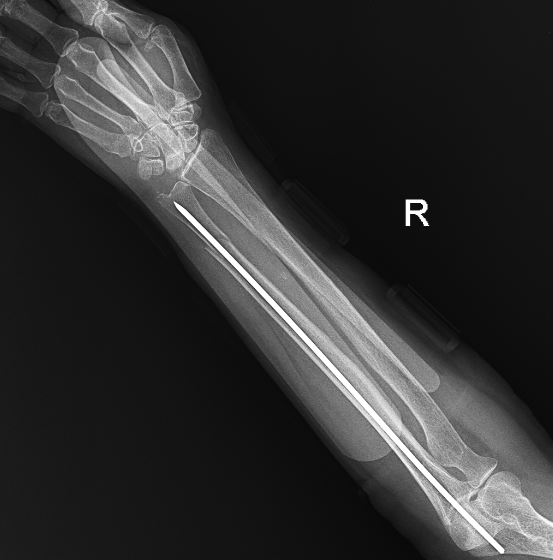

Hình ảnh xương đã được kết nối

Sau hội chẩn, ê-kíp lựa chọn phương pháp kết hợp xương xuyên đinh kín dưới hỗ trợ màn hình tăng sáng (C-arm). Đây là kỹ thuật ít xâm lấn, không cần mở ổ gãy, thực hiện qua đường rạch da nhỏ dưới hướng dẫn X-quang thời gian thực, giúp nắn chỉnh và cố định xương chính xác.

Phương pháp mang lại nhiều ưu điểm: giảm tổn thương phần mềm, hạn chế mất máu, rút ngắn thời gian phẫu thuật, giảm nguy cơ biến chứng và nhiễm trùng, giúp bệnh nhân giảm đau và phục hồi sớm. Đặc biệt phù hợp với người cao tuổi, nhiều bệnh lý phối hợp.

Sau phẫu thuật, bệnh nhân tỉnh táo, ổn định, giảm đau rõ rệt, vận động chi cải thiện tốt.